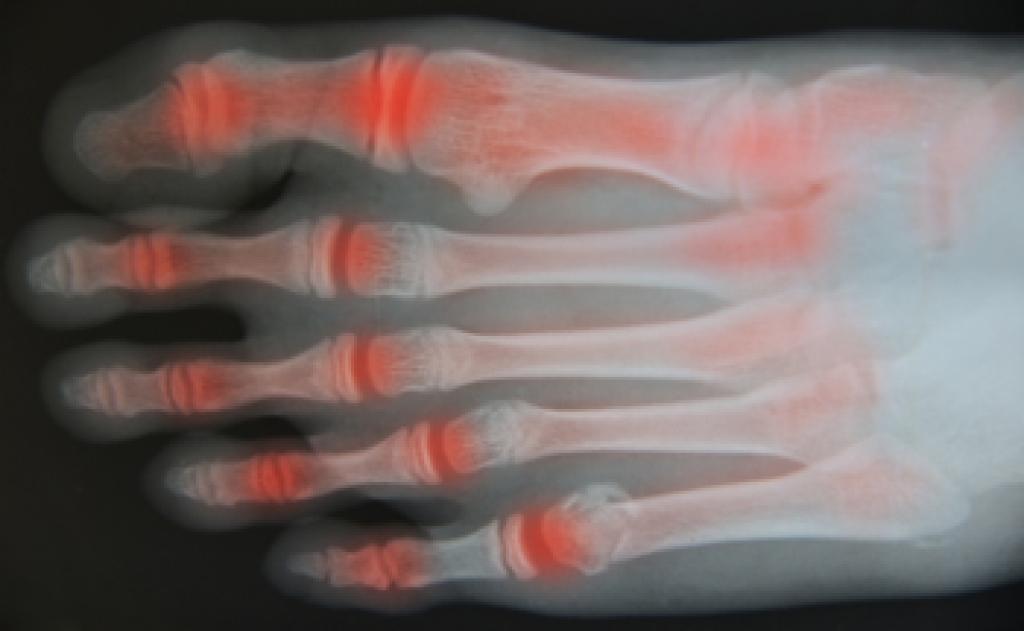

Is Rheumatoid Arthritis Common?

One of the most common types of arthritis is referred to as rheumatoid arthritis. Many people may experience symptoms of this condition in the feet and are aware of the pain and discomfort that typically exists with this ailment. There are specific symptoms that may accompany this type of arthritis, including swelling and soreness in the feet, difficulty waking, which may be a result of unstable joints, or the foot possibly changing shape. Research has shown the part of the foot that may be affected the most are the toes, which consist of smaller joints. They may begin to look deformed and may have difficulty in moving or bending. There may be additional foot conditions that may arise including the development of corns and calluses. This may be a result of changes in the foot shape. If you are afflicted with rheumatoid arthritis, it is suggested to consult with a podiatrist who can offer proper treatment techniques.

Because RA affects more than just your joints, including the joints in your feet and ankles, it is important to seek early diagnosis from your podiatrist if you feel like the pain in your feet might be caused by RA. For more information, contact Dr. John L. Coleman of Florida. Our doctor will assist you with all of your podiatric concerns.

What Is Rheumatoid Arthritis?

Rheumatoid Arthritis (RA) is an autoimmune disorder in which the body’s own immune system attacks the membranes surrounding the joints. Inflammation of the lining and eventually the destruction of the joint’s cartilage and bone occur, causing severe pain and immobility.

Rheumatoid Arthritis of the Feet

Although RA usually attacks multiple bones and joints throughout the entire body, almost 90 percent of cases result in pain in the foot or ankle area.

• Swelling and pain in the feet

• Stiffness in the feet

• Pain on the ball or sole of feet

• Joint shift and deformation